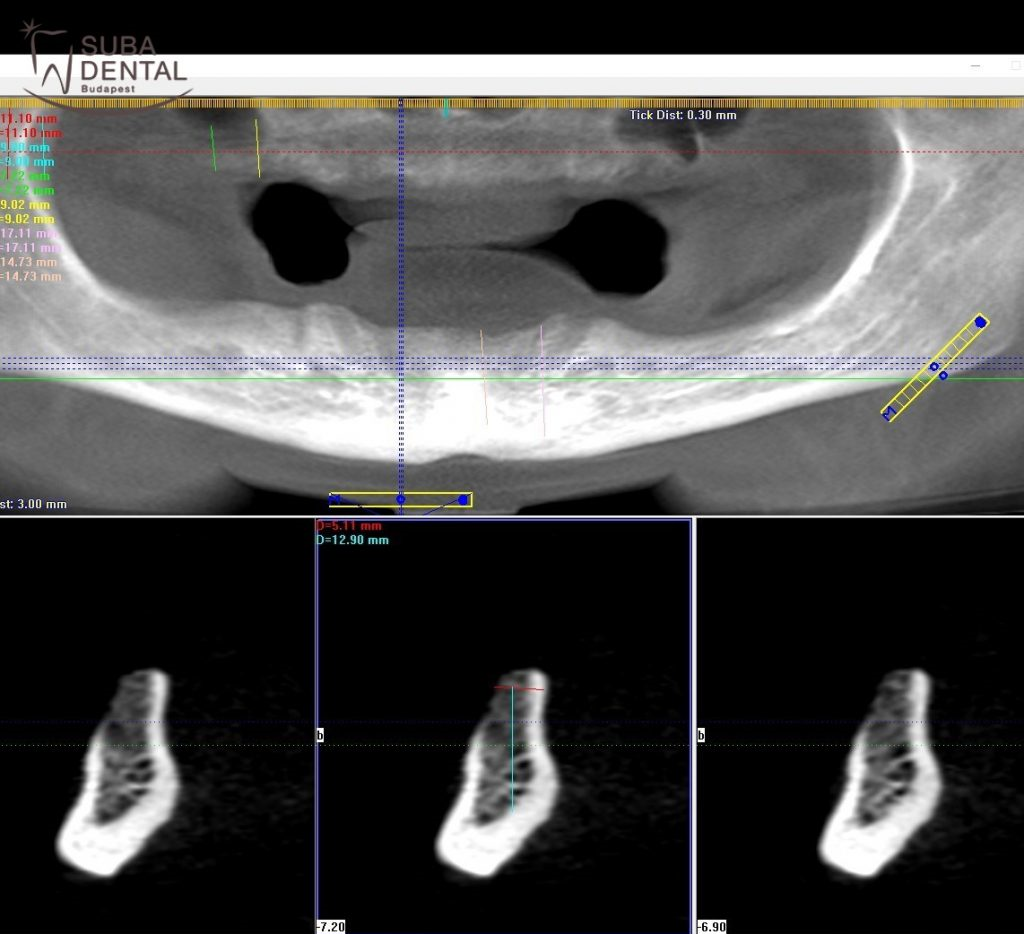

Après 3 mois de cicatrisation un scanner 3D (CBCT - Cone Beam Computed Tomography) a été réalisé pour examiner l'état de l’os en 3 dimensions. Basé sur le scanner, nous avons pu déterminer le lieu exact et la taille des implants. Nous avons posé 4-4 implants par mâchoire qui allaient tenir une barre de retention qui donnait une stabilité exeptionelle à la prothèse. La stabilité primaire des implants sur la mâchoire inférieure à l'implantation était supérieure à 30 Ncm, donc les implant ont été fermés avec des vis de cicatrisation (healing abutment). La stabilité des implants supérieurs n'atteignant pas 30 Ncm, alors seulement des vis de couverture ont été posées dans les implants. Après l’intervention, la gencive était fermée avec des sutures qui devaient être enlevées après 10 jours de cicatrisation. Les prothèses provisoires que la patiente a obtenues suivant l’extraction des dents ont été rebasées afin de pouvoir être portées de nouveau pendant les 6 mois de cicatrisation.

La région latérale du côté droite en bas sur le scanner CBCT. La photo du bas au milieu montre que l’hauteur de l’os est plus de 12 mm.